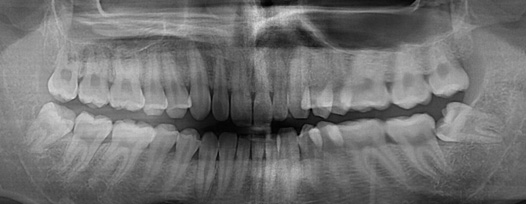

충치치료

정확한 진단으로 꼭 필요한 충치치료만을 진행합니다

충치치료는 정확하고 객관적인 진단이 가장 중요하며, 충치의 진행단계별로 적합한 치료를 진행해야 합니다.

충치가 있다는 말과 충치치료를 해야한다는 말이 같은 뜻은 아닙니다. 까맣게 보인다고해서 무조건 제거하고 떼워야하는 것은 아닙니다.

초기 충치의 경우 충치를 제거하기보다 그 충치가 더 진행되지 않게 예방하는 것이 더 중요하며, 이는 자연치아를 최대한 보존하고 불필요한 치료를 방지하는 방법입니다. 이를 위해서는 객관적이고 정확하게 충치의 단계를 진단하는 것이 필수적입니다.

청담네오플란트에서는 전문의료진들이 첨단 의료장비와 객관적인 시각자료를 통해 충치의 단계를 정확하게 진단하여 환자분들께 자세한 설명을 드린 후 단계 별로 꼭 필요한 치료만을 진행하고 있습니다.